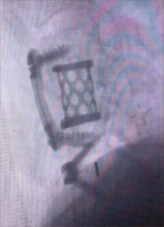

颈椎前路减压融合术适用于①屈曲型颈椎骨折或骨折脱位所致的颈椎创伤性不稳定;②颈椎爆裂性骨折,椎体粉碎,压迫脊髓或脊髓前动脉,产生脊髓前综合征,需做前路减压,解除脊髓受压。③后路广泛性椎板切除,颈椎不稳,经后外侧融合仍不牢固。目前我科已成功开展前路ACDF技术、ACCF技术、ROI-C插片技术、Zero-P零切迹技术,具有创伤小、恢复快、疗效佳,早期下床活动的优点。